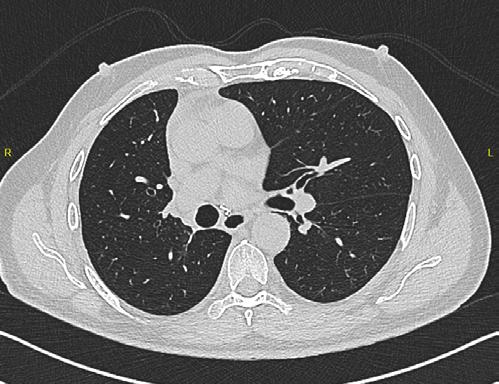

Se realiza cirugía con lobectomía inferior derecha, con resultado histopatológico de tumor carcinoide atípico, se realiza seguimiento con tomografía simple de tórax sin complicaciones en el lecho quirúrgico.

Figura 6. Estudio de seguimiento postlobotomía.